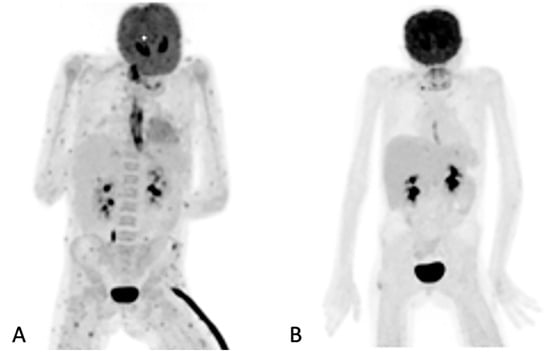

3.5. Added Value Due to the Metabolic Assessment of Lesions by Patient

In the 32 patients that had repeated [18F]FDG PET/CT imaging to assess the responses, the follow-up helped the clinicians to decide to stop, continue or change antifungal therapy (Figure 3). [18F]FDG PET/CT detected previously unknown IFI lesions in five patients of the 18 that were referred for the staging of the infection, which led to therapy prolongation in four and a change in therapy in one. In the 10 patients with indications of unexplained fevers or increasing infective markers, [18F]FDG PET/CT was found to be useful in four patients, as it guided the biopsy that led to the diagnosis of the IFI (see Figure 4). In the seven patients that were being prepared for ASCT, [18F]FDG PET/CT was considered to add value for all. In four patients, the [18F]FDG PET/CT allowed clinicians to proceed with the procedure; in two others, further antifungal therapy was provided with follow-up with [18F]FDG PET/CT, and a biopsy was conducted in one of the patients before ASCT was performed. Finally, in the six patients where scans was performed to assess metabolic activity in residual anatomic lesions, [18F]FDG PET/CT was considered useful. There was a complete metabolic response in five patients, and in two patients, further antifungal treatment was instituted. Table 5 tabulates the patients for which [18F]FDG PET/CT was deemed to have added value. Figure 4 shows a female patient with acute myeloid leukemia while on antifungal therapy, where [18F]FDG PET/CT explained the increasing infective markers by demonstrating multiple IFI lesions outside the thorax.

Figure 4. Sixty-three-year-old female with acute myeloid leukemia on treatment for pulmonary aspergillosis. [18F]FDG PET/CT was performed because there was unexplained fever, and the IFI lesions seen on HR CT (A) were similar to in the HR CT scan performed a month and 2 months earlier. [18F]FDG PET/CT scan (B) showed multiple IFI lesions outside the thorax, providing an explanation for the persistent fever.